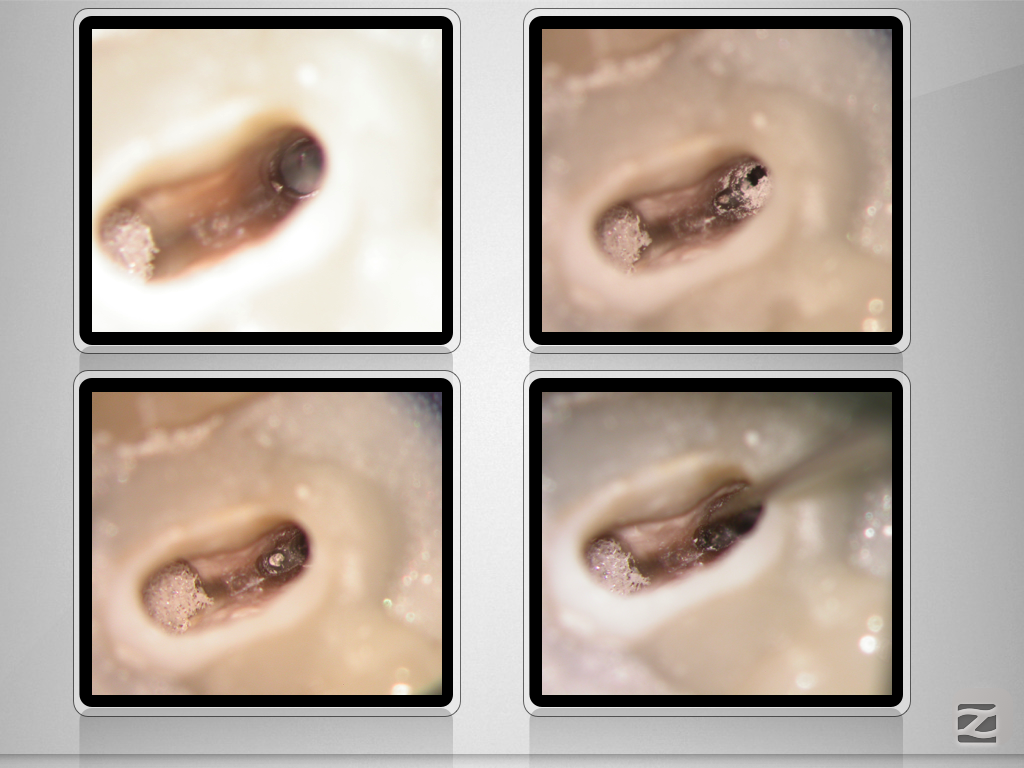

Immer schön skeptisch bleiben 3